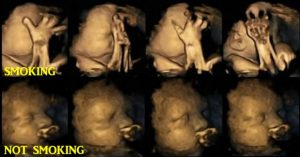

Pa parë imazhet, gjithëkush mendon se dëmtimet nuk janë aq të mëdha sa flitet, por teknologjia e fundit e ultratingujve 4D ka bërë të mundur që zhvillimi i fetusit të ndiqet hap pas hapi.

Studimi i kryer së fundmi nga hulumtuesit e Universitetit të Durham dhe Lancaster në Angli u botua në revistën Acta Paediatrica. 20 gra shtatzëna kanë marrë pjesë në studim për një periudhe tre-mujore; katër nga të cilat ishin duhanpirëse dhe tymosnin rreth 14 cigare në ditë. Efektet e njohura të pirjes së duhanit gjatë shtatzënisë janë: